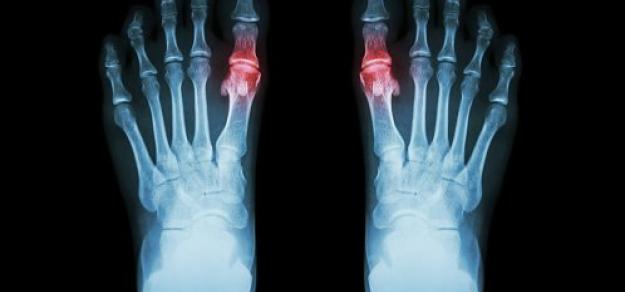

Asociación de enfermedad renal crónica con el uso de alopurinol en el tratamiento de la gota

JAMA Intern Med, 8 de octubre de 2018. En este estudio de cohorte de base poblacional del Reino Unido , el uso de alopurinol en pacientes con gota no aumentó el riesgo de disminución de la función renal, y se asoció significativamente con un riesgo 13% menor a dosis de 300 mg o más por día. Lo que significa que el alopurinol no parece estar asociado con una disminución de la función renal, y los médicos deben considerar otros contribuyentes potenciales cuando se enfrentan a una disminución de la función renal en pacientes con gota.

El ácido úrico está elevado…¿voy a tener gota?

Hay un relación directa entre el nivel basal de uricemia y el riesgo de presentar gota en los siguientes 15 años, desde un 1,1% para úrico menor a 6,5 mg/dL hasta 49% para valores de 10 mg/dL o más. Annals of the Rheumatic Diseases, febrero de 2018